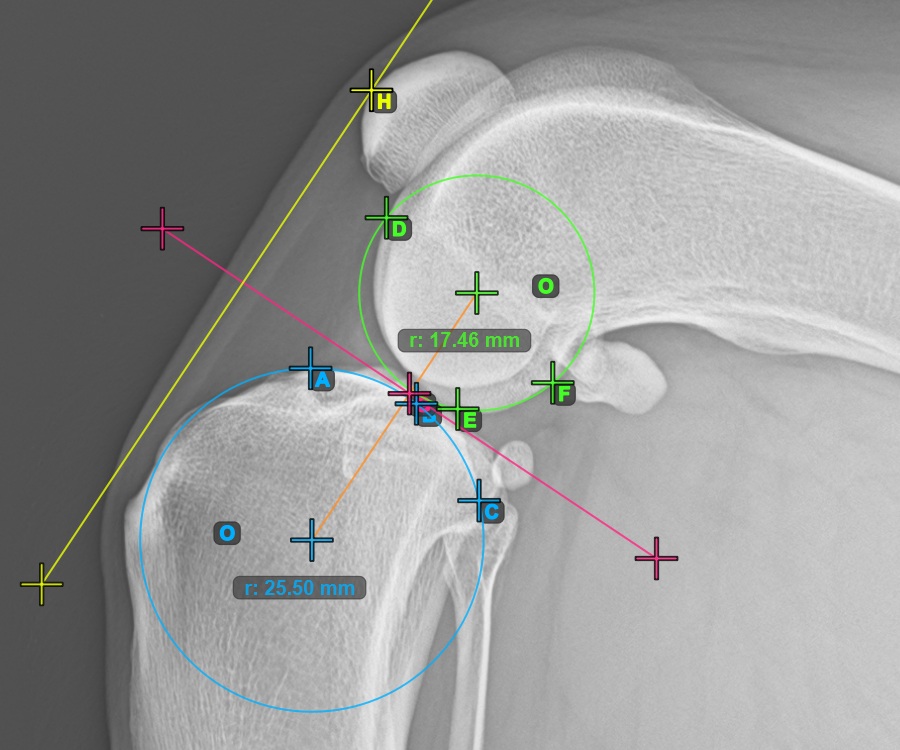

Mark one point in front of the joint on the common tangent between the two circles. A line will be drawn automatically through the marked point.

The image below represents a typical placement of the point on the common tangent between the two circles.